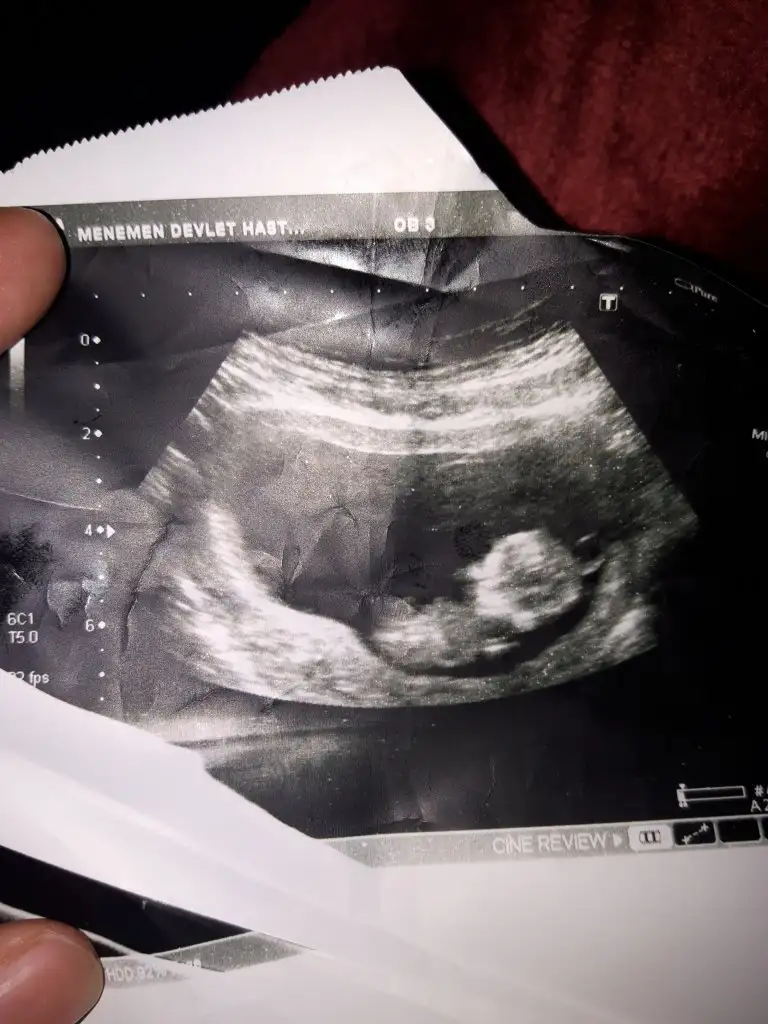

Nub özel mesajda 11 haftaya erkek 12 haftaya kız dedin balım keseye göre kızmı doktor 12 haftaya erkek gibi dedi saskoloz oldumBuna göre kız11 yada 12 hafta usg paylaştınızmı nubu uygunsa dogrulugu kesin

Buna göre erkek nub için 11yada 12 hafta usg paylaşın nub teorisi konu başlıgınaBenimkininde tahmin edermisiniz ikrameyra.☺☺☺☺☺

Karından bakıldıysa erkek vajinal ise kız 11 yada 12 hafta nub teorisine bakalımBen de yorum bekliyorum![]()

Onu hatırlamıyorum ama bu karından bunu da yorumlar mısınız? 6+3 görüntüsüKarından bakıldıysa erkek vajinal ise kız 11 yada 12 hafta nub teorisine bakalım![]()

Erkek buna göreOnu hatırlamıyorum ama bu karından bunu da yorumlar mısınız? 6+3 görüntüsü